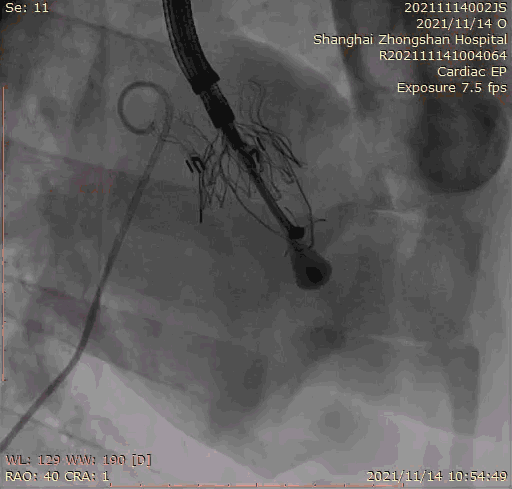

上海中山醫(yī)院葛均波院士、錢菊英院長、周達(dá)新教授、潘文志教授、潘翠珍教授、李偉教授共同完成此次臨床前研究。術(shù)后葛均波院士對Lux-Valve Plus的器械操作性能給予了高度評價,DSA和超聲影像也顯示出在本次研究中Lux-Valve Plus的安全性和有效性俱佳。

本次臨床前研究經(jīng)右側(cè)頸靜脈置入LuX-Valve Plus輸送系統(tǒng)可調(diào)彎鞘管,在DSA及超聲引導(dǎo)下將人工三尖瓣瓣膜植入到原有三尖瓣位置,利用獨(dú)特的錨定技術(shù)將人工瓣膜支架可靠固定在預(yù)定的位置。